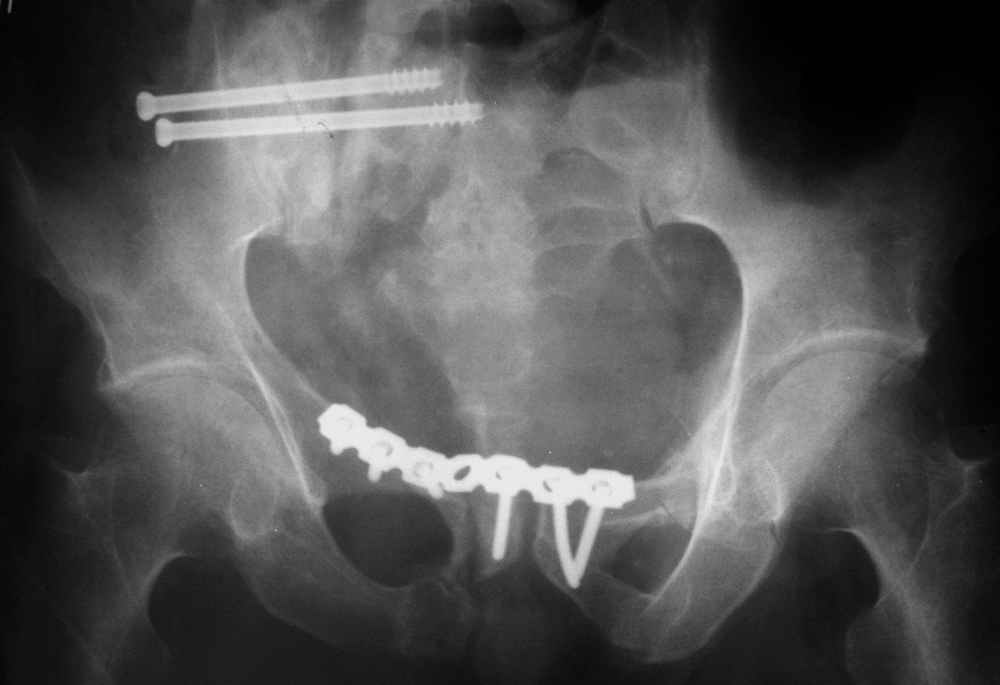

окончательная фиксация